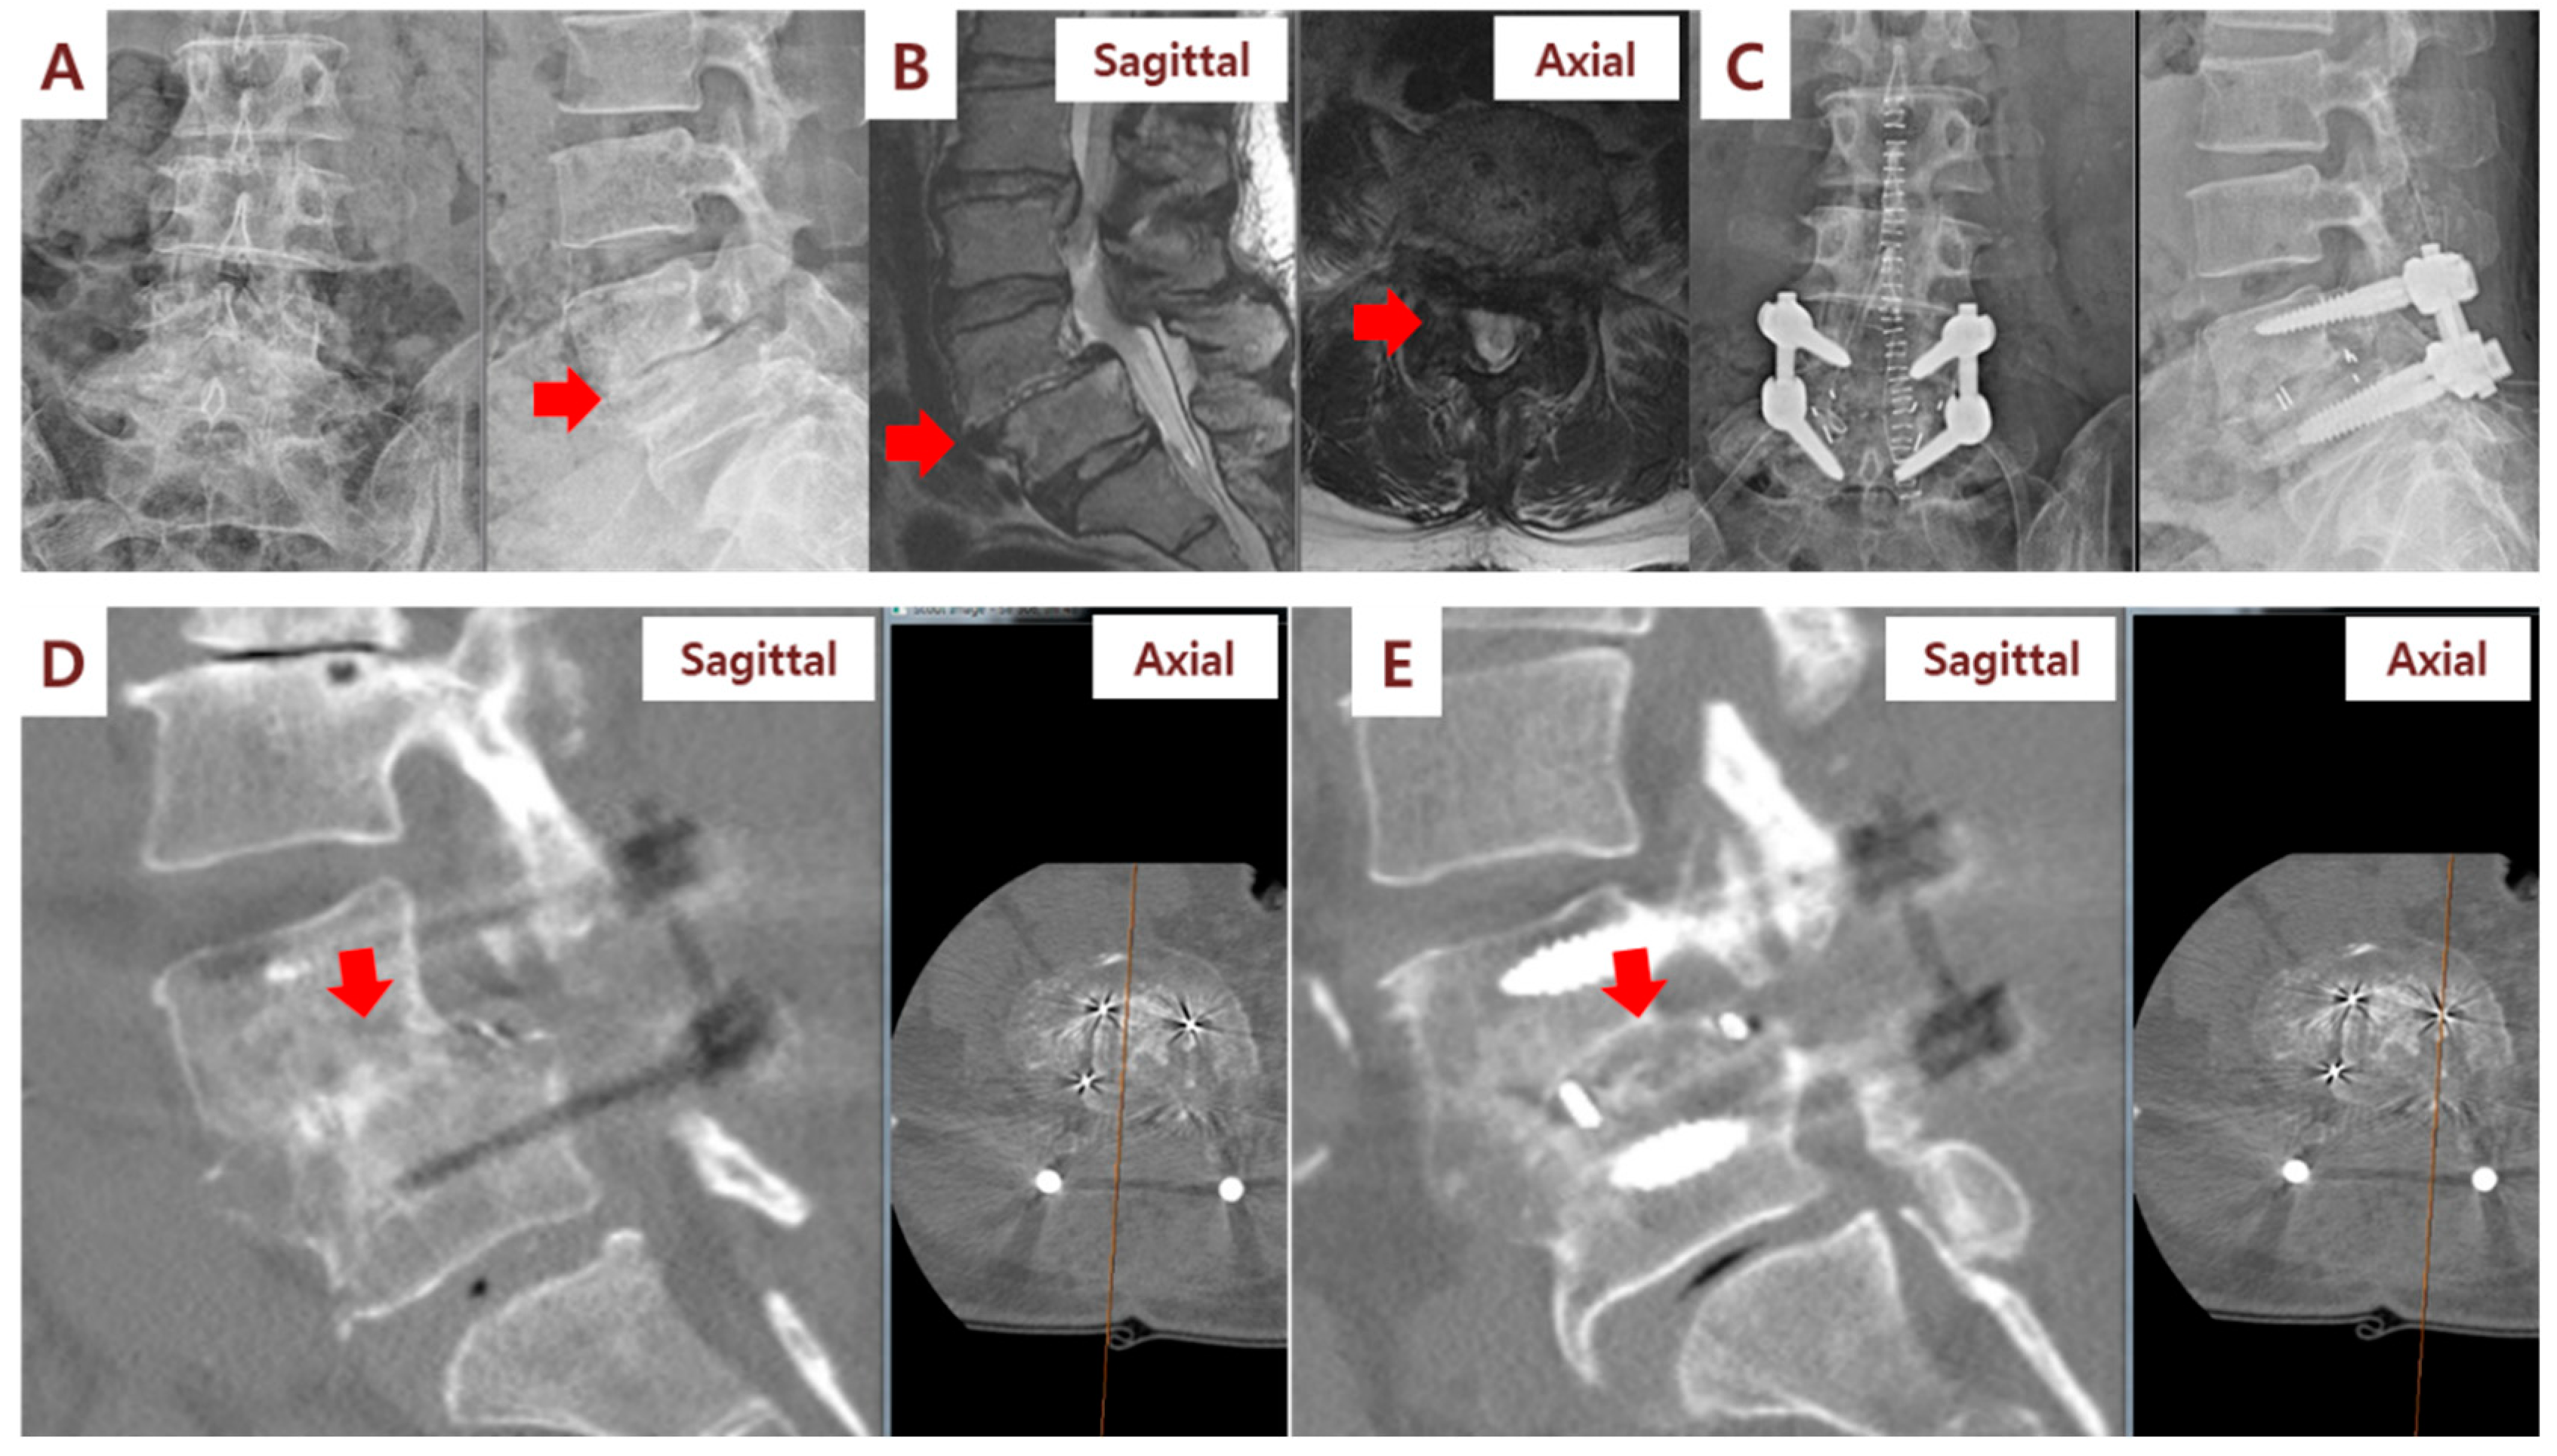

3.2. Clinical and Radiographic Outcomes